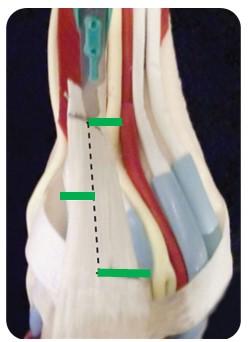

Figuur 2: Achillespees verlenging. We kijken naar de achterzijde van de enkel/hiel. De 3 groene streepjes zijn de scheurtjes in de Achillespees.